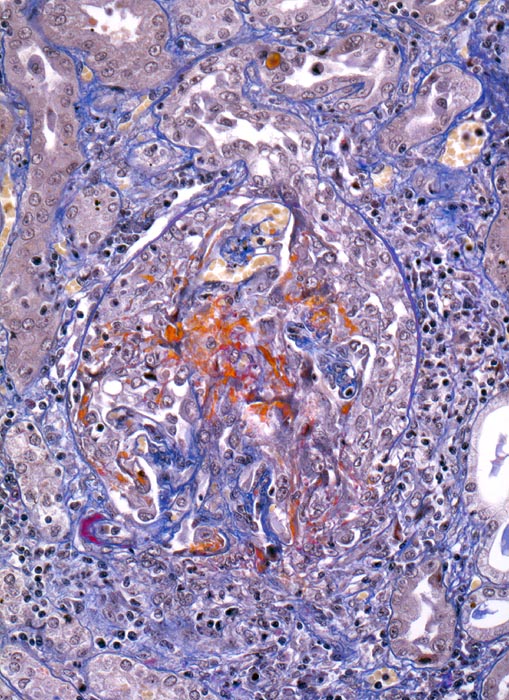

PathoPic – image database / PathoPic ID 5018 - extrakapilläre Glomerulonephritis bei Morbus Wegener

extrakapilläre Glomerulonephritis bei Morbus Wegener

Glomerulum mit Harnpol und Gefässpol mit geringer Arteriolosklerose des Vas afferens. Ausgedehnte Schlingennekrosen mit Exsudation von Fibrin und Ausbildung eines frischen rein proliferativen globalen Halbmondes. Einzelne erhaltene Schlingen sind ausgeweitet. Über der Schlingenruptur ist auch die Bowman'sche Kapsel rupturiert. An dieser Stelle findet sich eine periglomeruläre chronische Entzündung.

Rapid progressive Glomerulonephritis mit Entwicklung einer Oligurie innert weniger Tage. Fieber und Nachtschweiss. Chronische Sinusitis. cANCA erhöht.